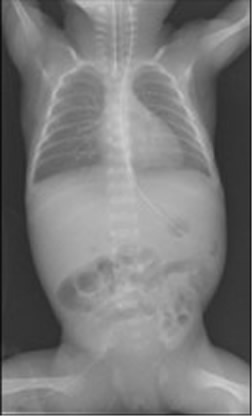

NICU(新生児集中治療室)内の未熟児の肺機能は未発達で、慢性肺疾患の発症リスクが高まります。この研究では生後直ぐの肺レントゲン画像から、36週時点での発症予測の研究を進めています。これにより、発症リスクが高い新生児には早期治療を始め、重症度の緩和や、発症を未然に防ぐことを目指しています。